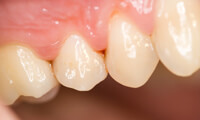

健康な歯肉

健康な歯ぐきは引き締まっていて、淡いピンク色をしています。毎日の正しいブラッシングと歯科医院での定期的な歯石除去(スケーリング)で健康な状態を維持していきましょう。